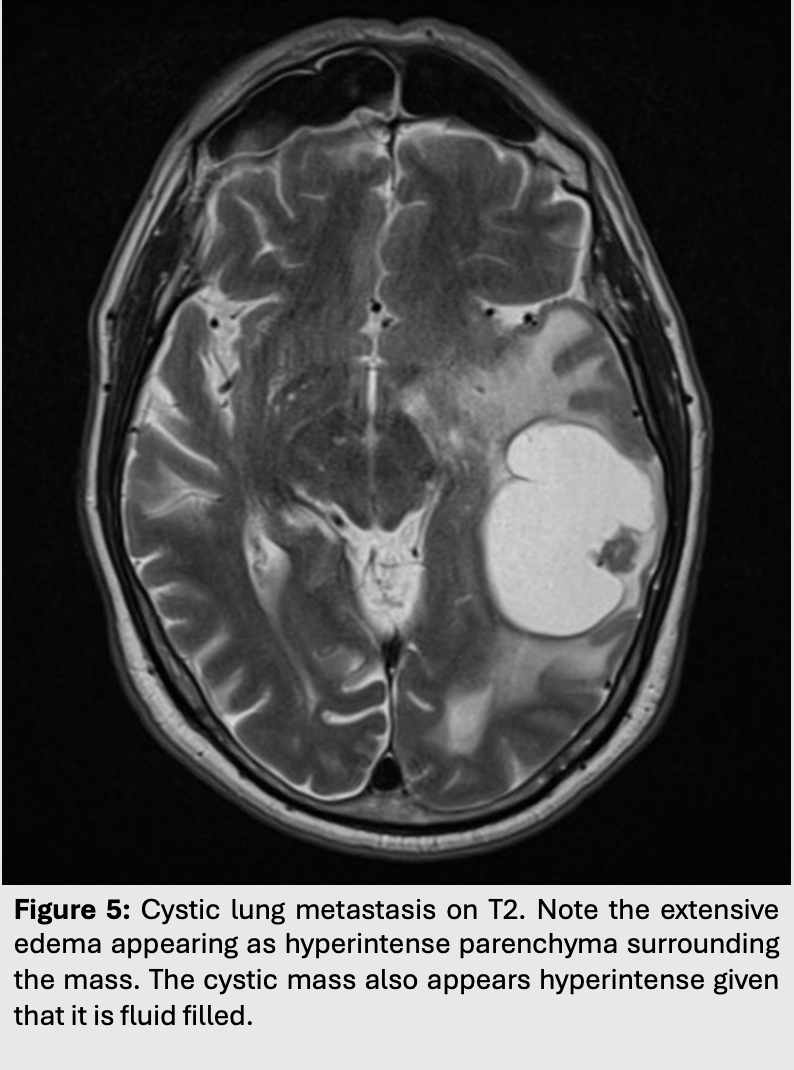

Figure 5: Cystic lung metastasis on T2. Note the extensive edema appearing as hyperintense parenchyma surrounding the mass. The cystic mass also appears hyperintense given that it is fluid filled.

Figure 6: Cystic lung metastasis on DWI. Notice how, contrary to the case of cytotoxic edema seen earlier, vasogenic edema does not come with fluid restriction and therefore there is no hyperintensity on DWI.

As such, vasogenic edema will appear hyperintense on T2/FLAIR but attenuated (hypointense) on DWI.

Vasogenic edema can be caused by many pathologies. Most commonly, it can be found surrounding intra-axial tumors, cerebral abscesses or even around maturing hemorrhages.